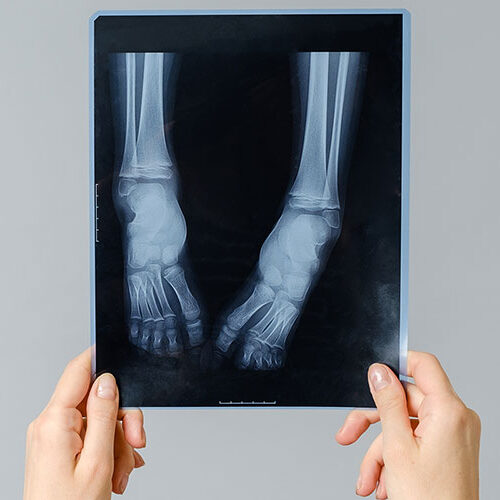

Ein Knochenbruch ist immer eine größere Verletzung!

Sie erfordert ein Röntgenbild. Eventuell muss der Knochen wieder gerade gerichtet werden.Die Ruhigstellung ist unterschiedlich. Äußerlich sind meist Gipse, oder Metallstangen, die im Knochen verankert werden. Innnerlich kommen Schrauben und Plättchen zur Anwendung. Bei diesen Versorgungen ist viel Erfahrung notwendig, um bleibende Schäden zu vermeiden.